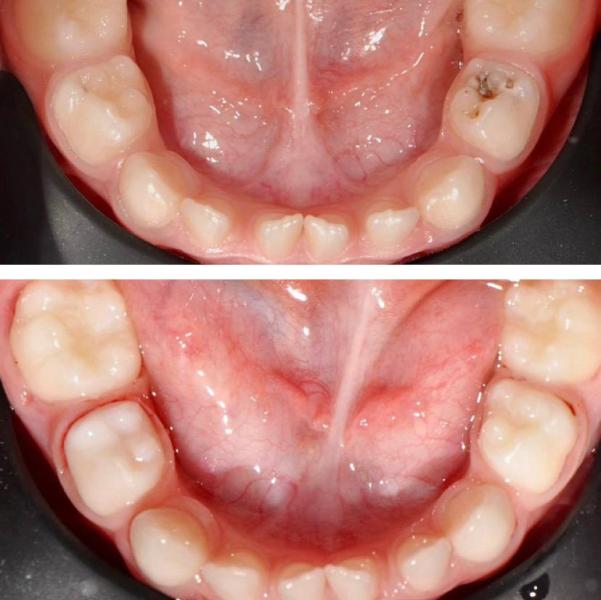

На фото большой труд и великолепный результат Петровой Татьяны Дмитриевны, руководителя детского отделения нашей клиники Iceberg с опытом работы более 8 лет!